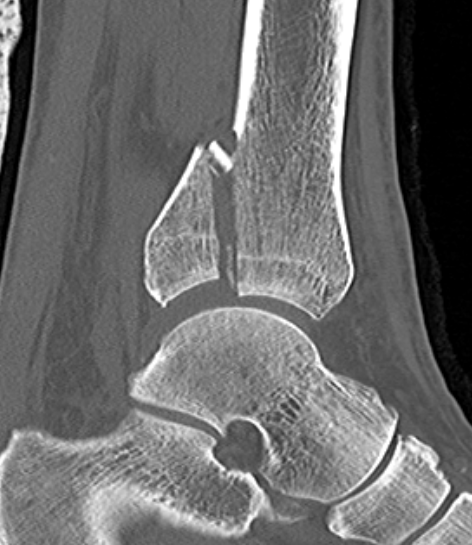

Mason and Malloy Classification

CT scan critical to classify and guide treatment / approach

| Type I | Type IIA | Type IIB | Type III |

|---|---|---|---|

| Avulsion of the PITFL |

Posterolateral fragment Volkmann fracture |

Posteromedial & posterolateral fragments Volkmann plus secondary fracture line |

Large coronal plane fragment Plafond fracture |